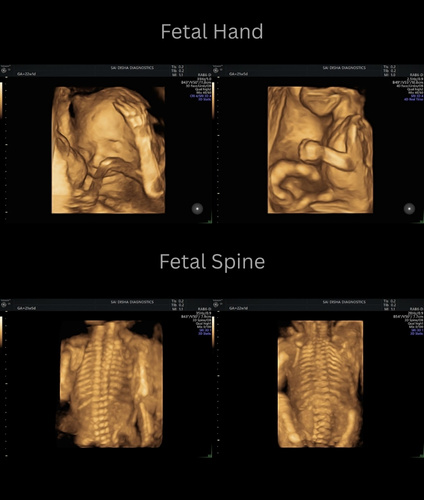

An ultrasound scan, also known as sonography, is a safe and non-invasive diagnostic procedure that uses sound waves to produce real-time images of the inside of the body. Unlike X-rays or CT scans, ultrasound does not use any radiation, making it especially suitable for monitoring pregnancies and for routine diagnostic imaging. During the procedure, a special gel is applied to the skin, and a device called a transducer is gently moved over the area of interest. The sound waves travel into the body and bounce back to create clear images of organs, tissues, and blood flow and fetus inside pregant mother.

Sai Disha Diagnostics offers high-resolution ultrasound imaging to support early and precise diagnosis across a wide range of medical conditions.